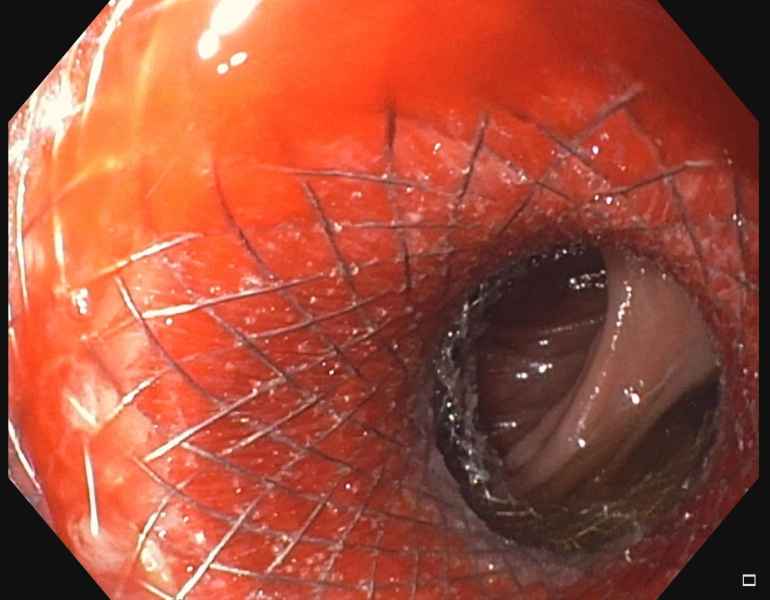

An exotic case of duodenal obstruction

Fotografia